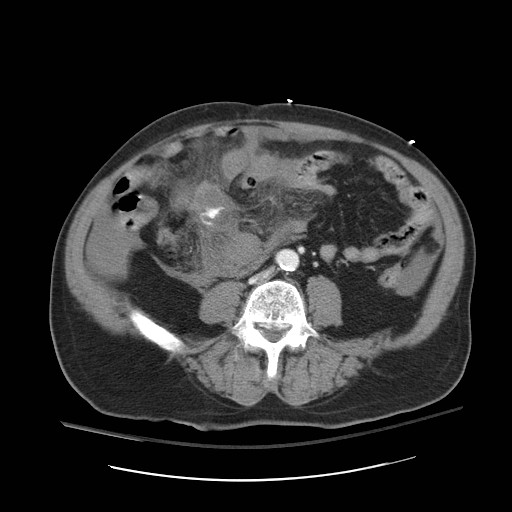

Imaging interpretation is a vital skill required for all those dealing with the multiply injured patient, not just the radiologist.

Management in trauma follows the ABCDE approach and radiological interpretation is no different. Consultant Radiologist Dr Nick Carter guides us through interpretation of the CT pan-scan as the radiology primary survey in trauma.

Images courtesy of Dr Derek Smith, Radiopaedia.org from the case rID: 36667, Dr Sajoscha Sorrentino, Radiopaedia.org from the case rID: 16291 and Dr Maxime St-Amant, Radiopaedia.org from the case rID: 20112